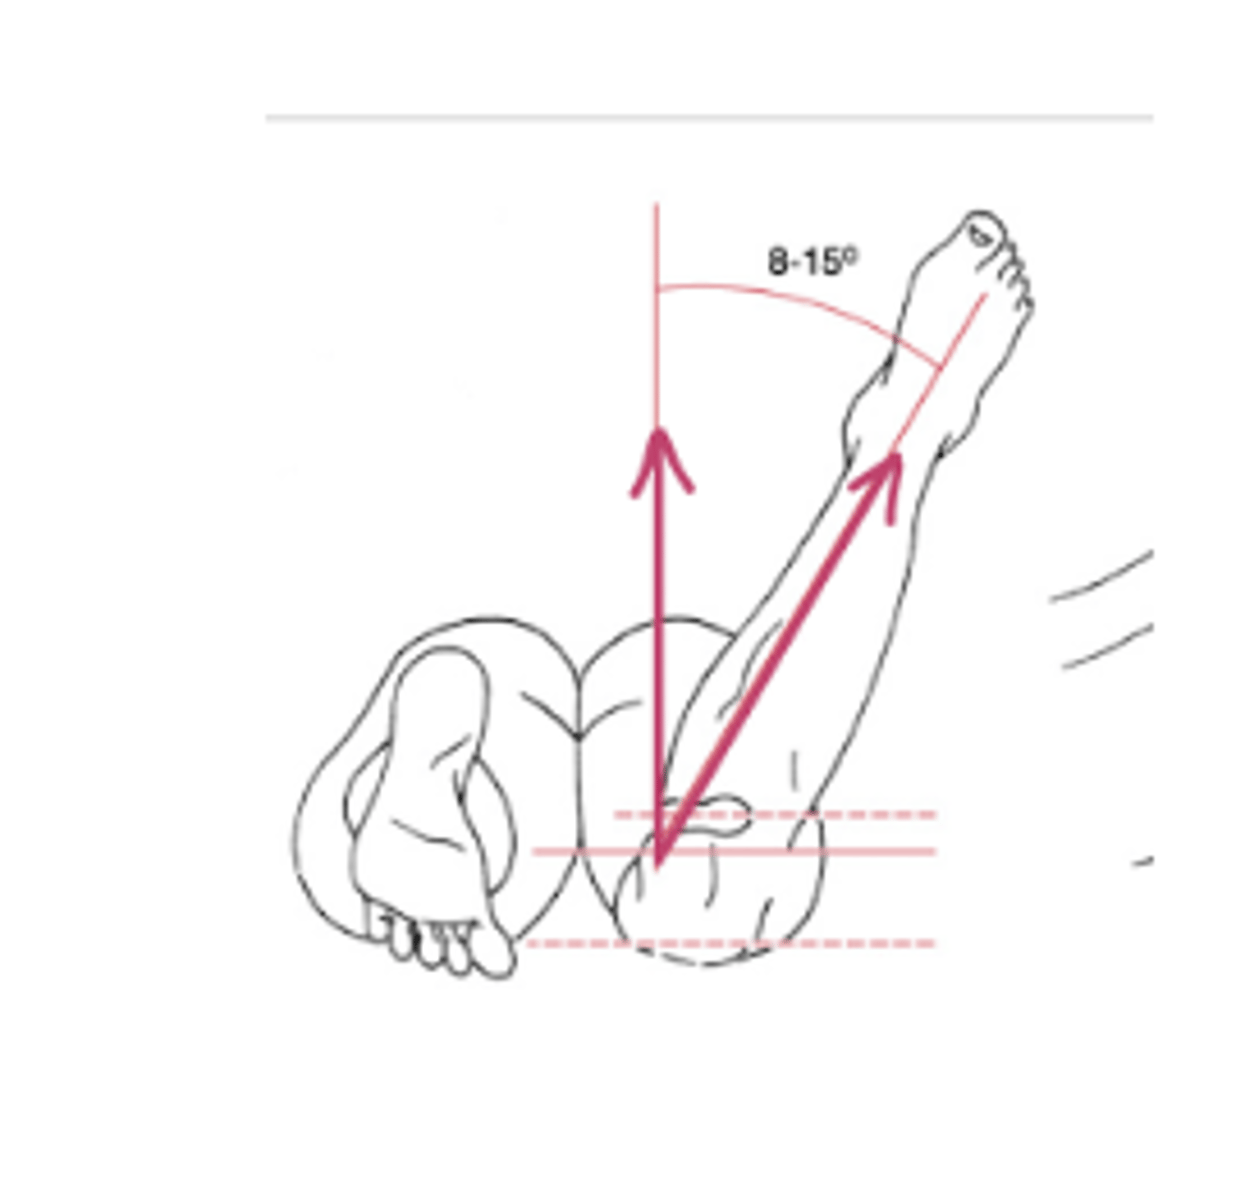

Craig Test

Normal males: 8-12 degrees

Normal females: 12-18

Put hand on greater trochanter and IR/ER femur

Tests for femoral anteversion → if lots of IR you have anteversion